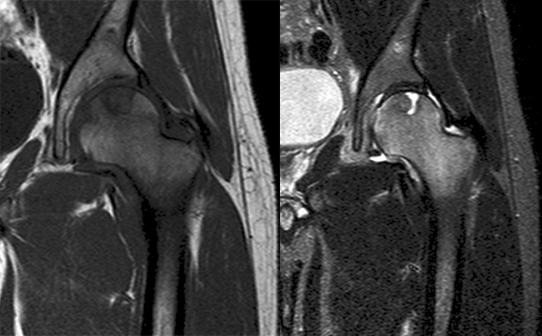

肿瘤对软骨的破坏

肿瘤对骨骺板和关节软骨的破坏是对骨破坏的继续。缺乏血管的骨骺板对恶性肿瘤有抵抗作用,骨骺板可暂时阻止肿瘤的蔓延,但当肿瘤进一步发展时, 骨骺板亦可被破坏,X 线平片或 CT 可表现为先期钙化带密度减低、中断或消失。MRI 可显示肿瘤从干骺端跨越骨骺板侵犯骨骺(图 15、图 16)。肿瘤突破关节软骨向关节腔发展时, 可表现为关节面破坏、塌陷(图 17), 关节腔内出现软组织肿块。少数良性骨肿瘤如软骨母细胞瘤, 亦可超越骺板向两侧发展或突入关节腔内, 此为肿瘤膨胀生长所致, 而非浸润性破坏。

图 15.骨骺板破坏:骨肉瘤

图 16.骨骺板破坏:骨肉瘤